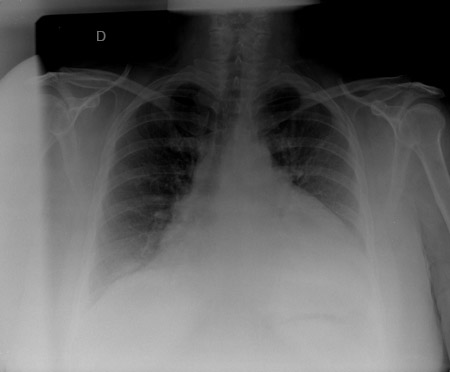

Radiografia torácica

A radiografia torácica pode mostrar uma silhueta cardíaca em formato de garrafa d'água com uma faixa de gordura pericárdica evidente, sugerindo um grande derrame pericárdico. Pode haver também derrames pleurais.[Figure caption and citation for the preceding image starts]: Radiografia torácica em um paciente com derrame pericárdico mostrando achados típicos de uma silhueta cardíaca em formato de garrafa d'água com uma faixa de gordura pericárdica evidenteDo acervo do Dr. Rajdeep Khattar [Citation ends].